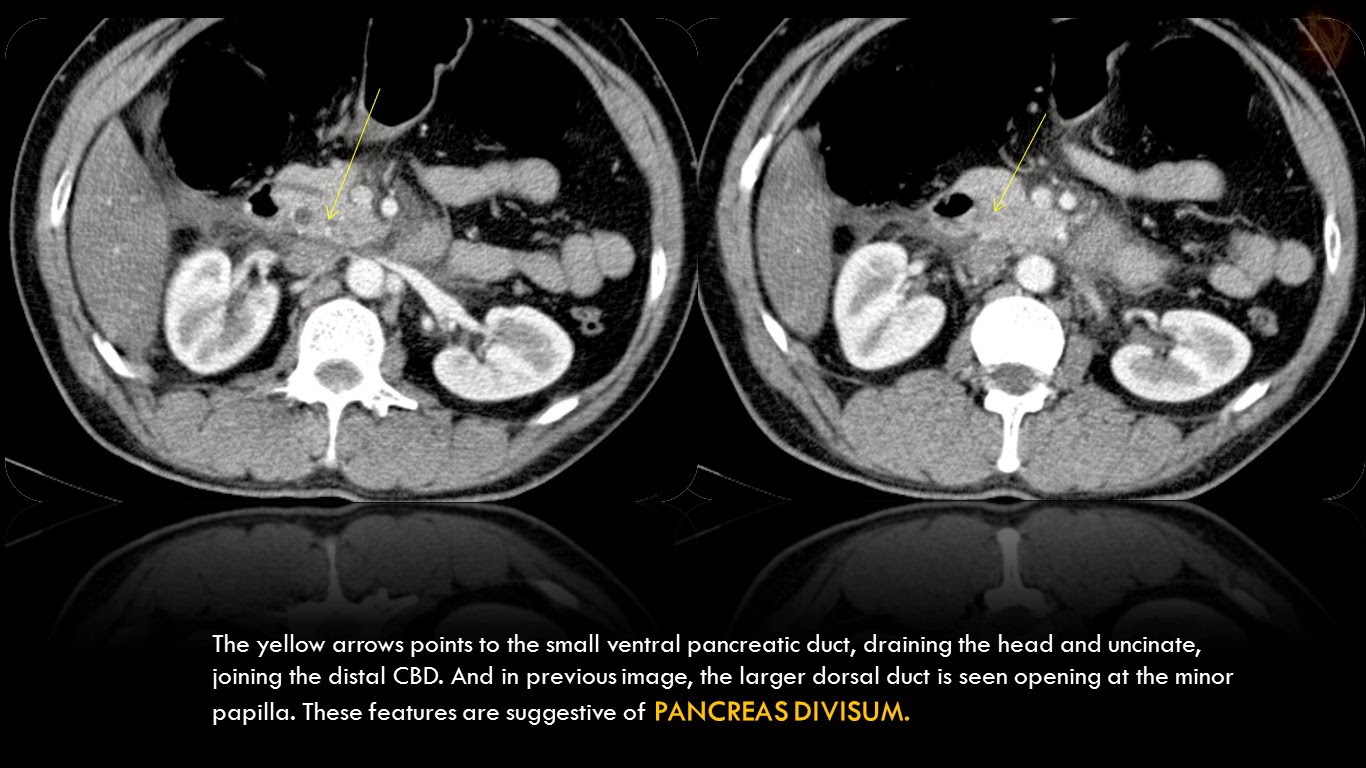

figure pancreas divisum showed suggestive blockage duct pancreatic main.

divisum pancreas duct ct ventral figure acute pancreatitis bmj case intraductal papillary neoplasms mucinous casereports larger version bcr powerpoint.

divisum duct pancreas ventral bmj figure intraductal mucinous neoplasms acute pancreatitis papillary larger version case mri pancreatic casereports powerpoint.